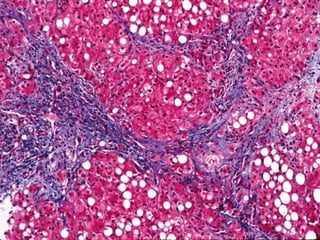

1 .High-power view of hepatic macrosteatosis and microsteatosis. The small intracellular fat

vacuoles give the hepatocytes a foamy appearance. Note megamitochondria (arrowhead)

(hematoxylin-eosin).

2. High-power view of hepatocytes containing Mallory bodies. The chemotaxis of the denatured

cytokeratin filaments attracts neutrophils (hematoxylin-eosin).